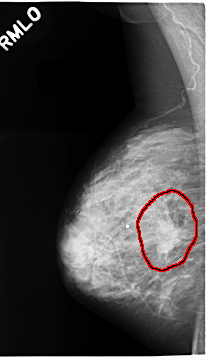

C_0064_1.RIGHT_MLO

FILE: C_0064_1.RIGHT_MLO.OVERLAY

TOTAL_ABNORMALITIES 1

ABNORMALITY 1

LESION_TYPE CALCIFICATION TYPE AMORPHOUS DISTRIBUTION CLUSTERED

LESION_TYPE MASS SHAPE IRREGULAR MARGINS SPICULATED

ASSESSMENT 5

SUBTLETY 5

PATHOLOGY MALIGNANT

TOTAL_OUTLINES 1

BOUNDARY